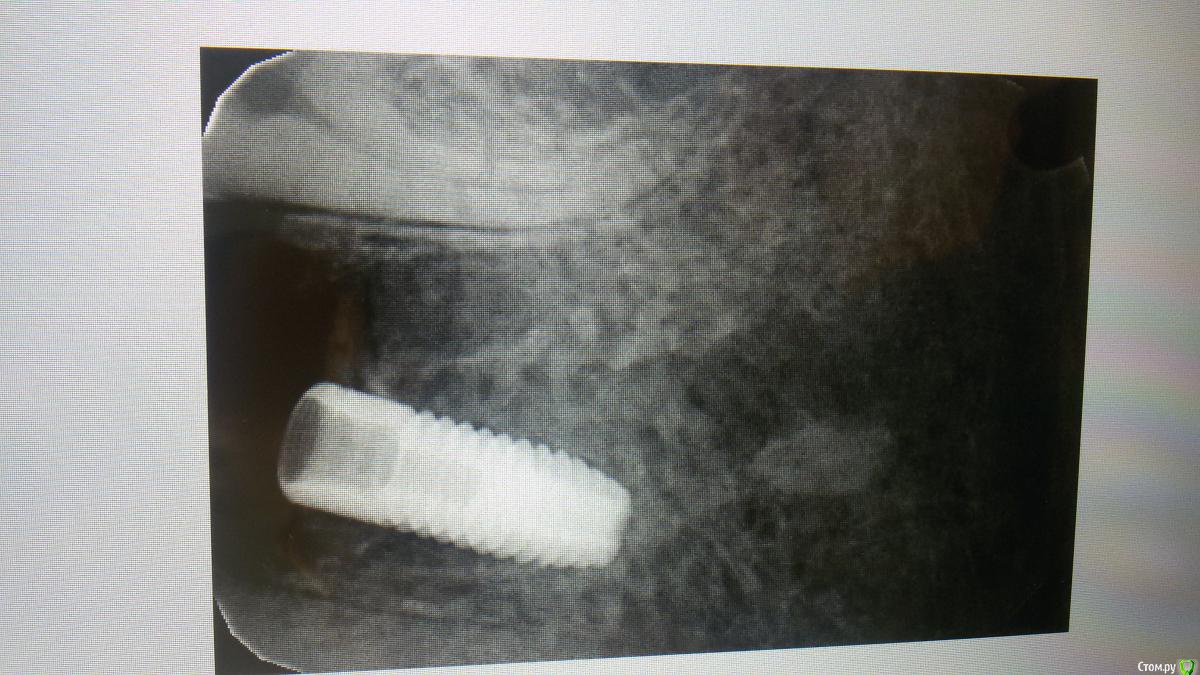

Бандерлога Опубликовано 7 октября, 2019 Поделиться Опубликовано 7 октября, 2019 Приветствую, коллеги. Случилась очередная изжога, как выразился мой товарищ. 22 дня назад он поставил имплантат Астра 4.0 х 11.0. Удаление было 3 мес. назад, после удаления развился альвеолит, лечили с применением альважиля. Со слов коллеги во время препарирования кость была рыхлая, отмечалось наличие волокон альважиля. Сверлился по протоколу для мягкой кости, последнее сверление фреза 3,7 в пределах кортикалки. Торк не получил, установил миллиметровую заглушку и ушился. Пациент был на осмотре через 3 дня, все нормально, когда явился на снятие швов через 10 дней, стало видно, что заглушка прорезалась через слизистую, и свободно там залегает. Заглушку удалил, и более делать ничего не стал. Сегодня пациент должен был прийти на осмотр, но не смог, явится завтра - что делать теперь?!. Советовал установить, сразу после прорезывания заглушки, новую 0 мм., и ждать. Но получилось так. Какие перспективы ожидать. Ссылка на комментарий

El_cucuy Опубликовано 22 января, 2020 Поделиться Опубликовано 22 января, 2020 (изменено) 1) поставить низкую заглушку, подшить сверху трансплантат под лоскутки 2) не делать ничего до интеграции, решать вопросы на втором этапе Доброго времени суток , доктора . По состоянию на 20 декабря , вот такая картина , нужно ли подсаживать трансплантат? Изменено 22 января, 2020 пользователем El_cucuy Ссылка на комментарий